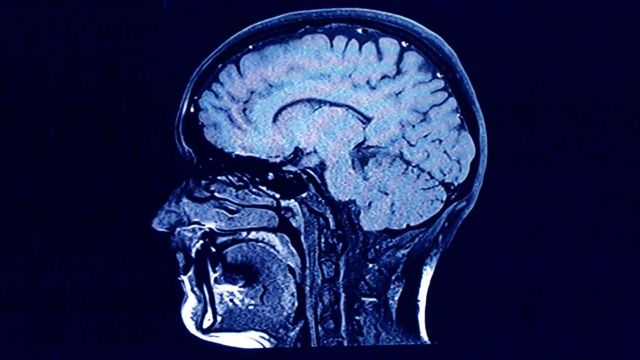

வயது முதிர்ந்த காலத்திலும் மனித மூளையில் புதிய நியூரான் செல்கள் உருவாகுமா என்ற கேள்விக்கான விடையை அறிய கார்பன் டேட்டிங் நுட்பம் பயன்படுகிறது.

ஸ்பால்டிங் மற்றும் அவரது சகாக்கள், மனித மூளை செல்களான நியூரான்கள் தொடர்பாக, கார்பன் டேட்டிங் நுட்பத்தை பயன்படுத்தி, 2013 இல் ஆய்வுகளை மேற்கொண்டனர். மனித மூளை செல்களுக்குள் உள்ள நியூரான்களின் எண்ணிக்கை, ஒருவரின் குழந்தைப் பருவத்திலேயே நிர்ணயிக்கப்பட்டுவிடுவதாக, பல ஆண்டுகளாக ஆராய்ச்சியாளர்கள் கருதி வந்தனர்.

மூளையின் கார்டெக்ஸ் பகுதியில், ஸ்பால்டிங் குழுவினர் மேற்கொண்ட முந்தைய ஆய்வுகளின் முடிவுகள் நியூரான்கள் குறித்த ஆராய்ச்சியாளர்களின் புரிதலை பிரதிபலிப்பதாகவே இருந்தன.

ஆனால், மூளையின் ஹிப்போகாம்பஸ் பகுதியில், கார்பன் டேட்டிங் முறையை கொண்டு மேற்கொண்ட ஆய்வில், ஒருவர் முதுமைப்பருவம் எட்டிய பிறகும், அவரது வாழ்நாள் முழுவதும் புதிதாக நியூரான்கள் உற்பத்தி செய்யப்படலாம் என்பதை ஸ்பால்டிங் குழு கண்டறிந்தது.

நரம்பியல் மருத்துவத்தில் முக்கிய முன்னேற்றமாக கருதப்படும் இந்த ஆய்வு முடிவு, நோய்களின் மூலம் ஏற்படும் நியூரான் இழப்பை தடுக்கவும், புதிய நியூரான்களின் எண்ணிக்கையை அதிகரிப்பதற்கான மருத்துவ உத்திகளுக்கு வழிவகுத்தது.